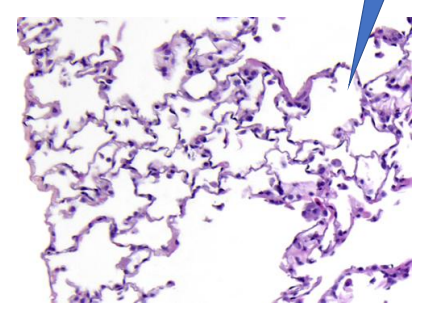

Normal lung

—> alveoli

Pulmonary oedema

—> alveolar spaces filled with hematogenous eosinophili susbtace = edematoeuos fluid

1- oedematous fluid

Pulmonary odema

—> alveolar spaces filled with hematogenous esinophilic substance = edematous fluid